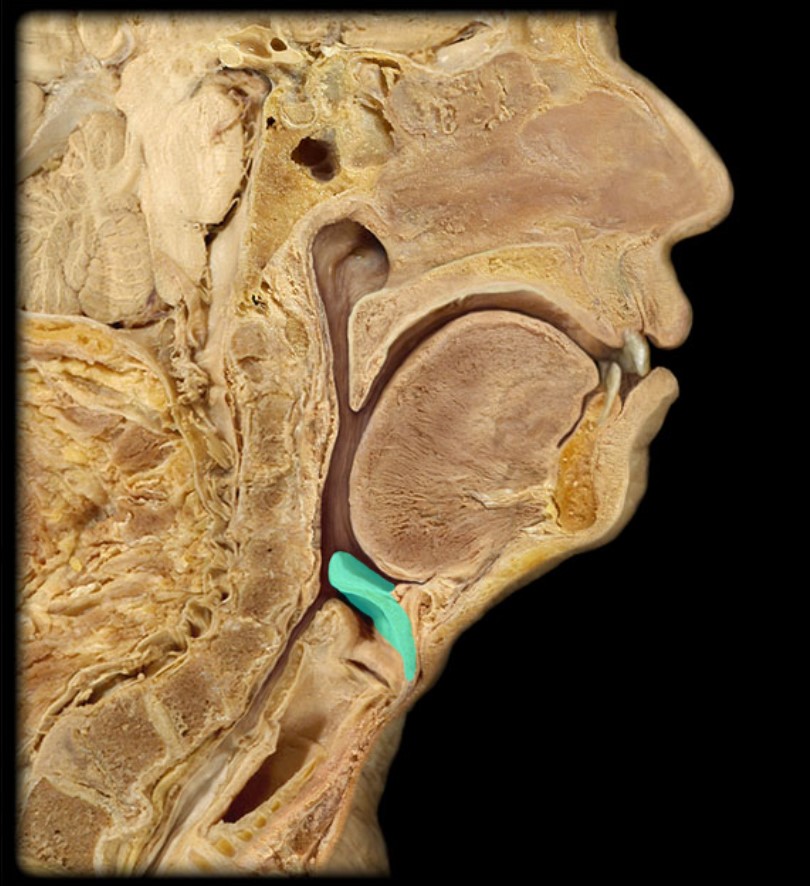

Anatomy 5 - Bifurcated Skull

29 Terms

1

New cards

Thyroid Gland

(Donor Only)

2

New cards

Atlas

3

New cards

Vertebral Artery

(Donor Only)

4

New cards

Nasal Septum

(Donor Only)

5

New cards

Esophagus

6

New cards

Trachea

7

New cards

Vocal Fold

8

New cards

Epiglottis

9

New cards

Hyoid

10

New cards

Mandible

11

New cards

Mylohyoid

12

New cards

Geniohyoid

13

New cards

Genioglossus

14

New cards

Lingual Tonsil

15

New cards

Palatine Tonsil

16

New cards

Uvula

17

New cards

Soft Palate

18

New cards

Palatine Bone

19

New cards

Maxilla

20

New cards

Pharyngeal Tonsil

21

New cards

Auditory Hiatus

22

New cards

Torus Tubarius

23

New cards

Sphenoid Sinus

24

New cards

Inferior Nasal Concha

25

New cards

Middle Nasal Concha

26

New cards

Superior Nasal Concha

27

New cards

Nasal Vestibule

28

New cards

External Nares

29

New cards

Frontal Sinus